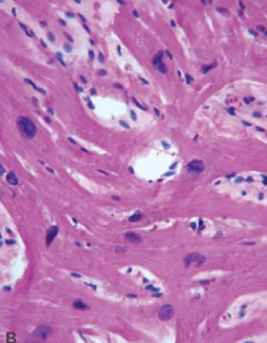

Hypertrophic Cardiomyopathy

Myocyte disarray, extreme hypertrophy, and characteristic branching, & interstitial fibrosis.